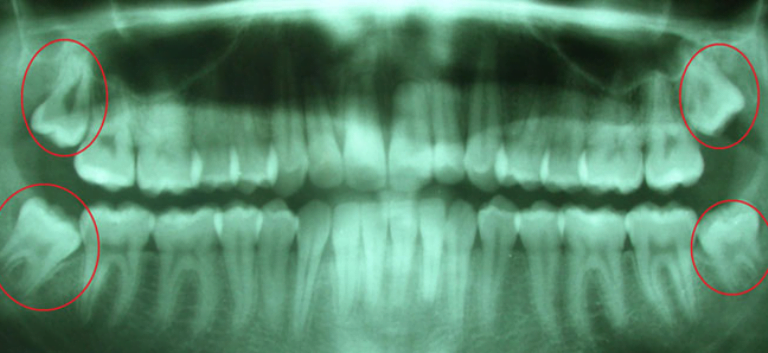

Las famosas muelas de juicio, mejor conocida como cordales, son los últimos molares en aparecer y pueden llegar a causarte un gran dolor de cabeza o de oído. Ellas son cuatro y van ubicados en los cuadrante de la boca, pueden exhibirse entre los 17 y 20 años, pudiendo incluso nunca dar señales de vida.

Existen muchos casos en los que las cordales salen de manera vertical, afectando las raíces de los demás dientes y deformando la dentadura. A pesar de que hay personas que tienen edad avanzada y aun no se han manifestado, es necesario extraerlas, duelan o no, debido a que producen problemas de articulaciones.

Existen dos razones importantes para extraer las muelas de juicio; la primera, cuando se va a comenzar un tratamiento de ortodoncia para mejorar la posición de los dientes y, la segunda, porque no hay espacio suficiente para su estadía en la superficie.